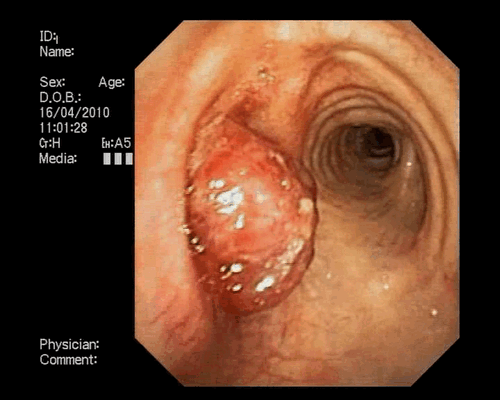

Краткое описание. В области ректо - сигмоидного отдела имеется циркулярное сужение за счет плотной бугристой ткани, просвет сужен более чем на 2/3, протяженность около 6 см. Рельеф поверхности неоднородный, местами не дифференцируется. Патолого - гистологическое исследование № ***52. 25.05.2022 г. В присланном материале обнаружены кусочки толстой кишки, часть из которых сохранного строения, представленные анаплазированными тубулярными, криброзными и солитарными структурами. Клетки эпителия толстокишечного типа с выраженным клеточно - ядерным полиморфизмом, высоким ядерно - плазматическим соотношением, умеренно выраженной митотической активностью. Строма скудная, с диффузной полипорфноклеточной инфильтрацией. Закл.: Низкодифференцированная G3 аденокарцинома толстой кишки.